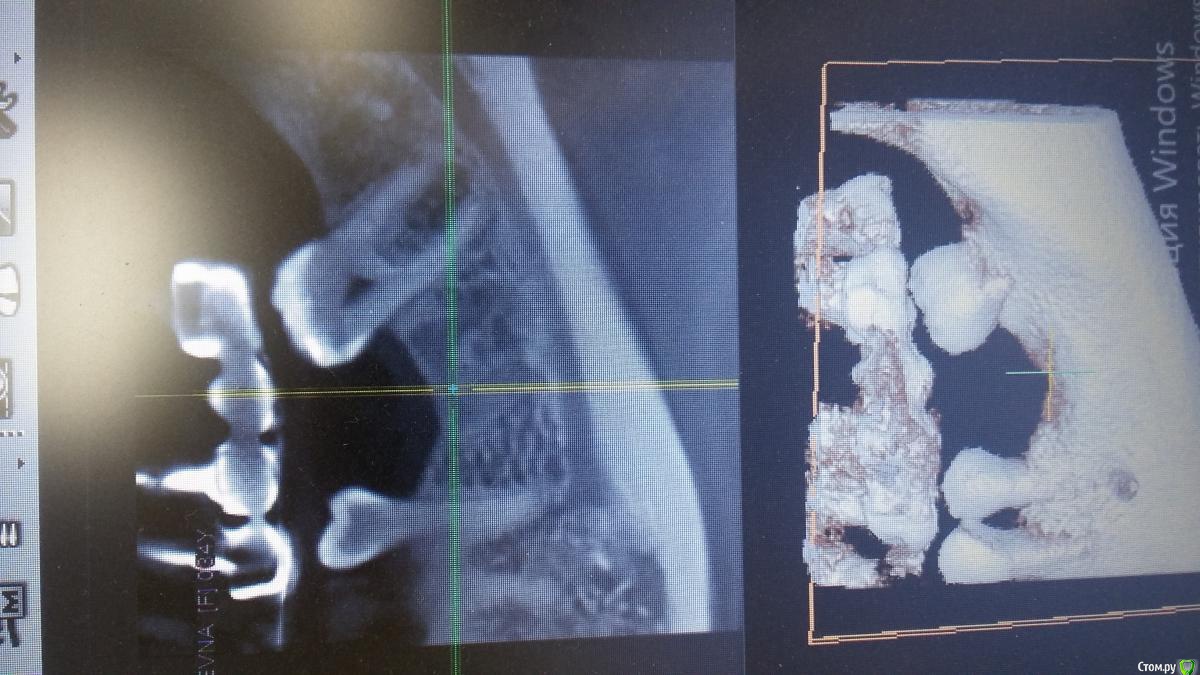

Антон 123 Опубликовано 30 марта, 2019 Поделиться Опубликовано 30 марта, 2019 Добрый день уважаемые форумчане. Посмотрите пожалуйста на скрины. Планируется имплантация 36 . Смущает что удаление было 5 лет назад,а на кт очертания удаленного зуба как будто на прошлой неделе! Ссылка на комментарий

Антон 123 Опубликовано 30 марта, 2019 Автор Поделиться Опубликовано 30 марта, 2019 Вот скрины. Заранее спасибо за мнение опытных товарищей Ссылка на комментарий

Антон 123 Опубликовано 30 марта, 2019 Автор Поделиться Опубликовано 30 марта, 2019 Молодая девушка. Возраст 30 лет. Удаление 36 зуб 5 лет назад. Десна ровная. Жалоб нет. Думаю имплантировать. Кто,что скажет,можно имплантировать? Ссылка на комментарий